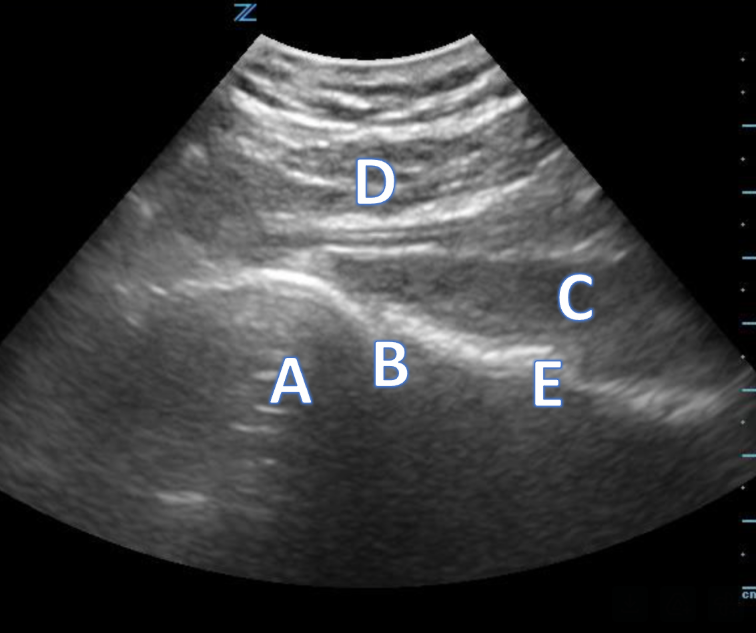

Shoulder

A 43-year-old male is complaining of right shoulder pain after a fall playing pickup soccer. You obtain an ultrasound image (Image 1) of the area with the findings below. What is your diagnosis? Can you identify the structures? A comparison image (Image 2) of the left unaffected shoulder is also provided.